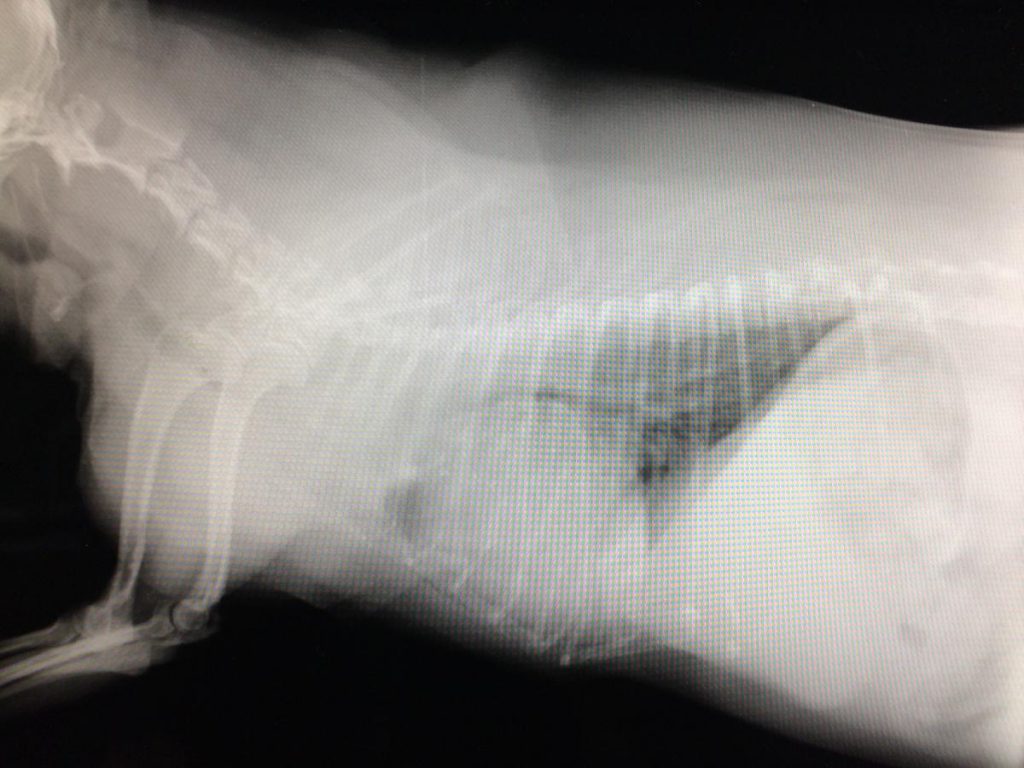

異物誤食・消化管内異物

オモチャを誤飲した犬の胃切開手術

異物誤食について

タオルケットを誤食したワンちゃん